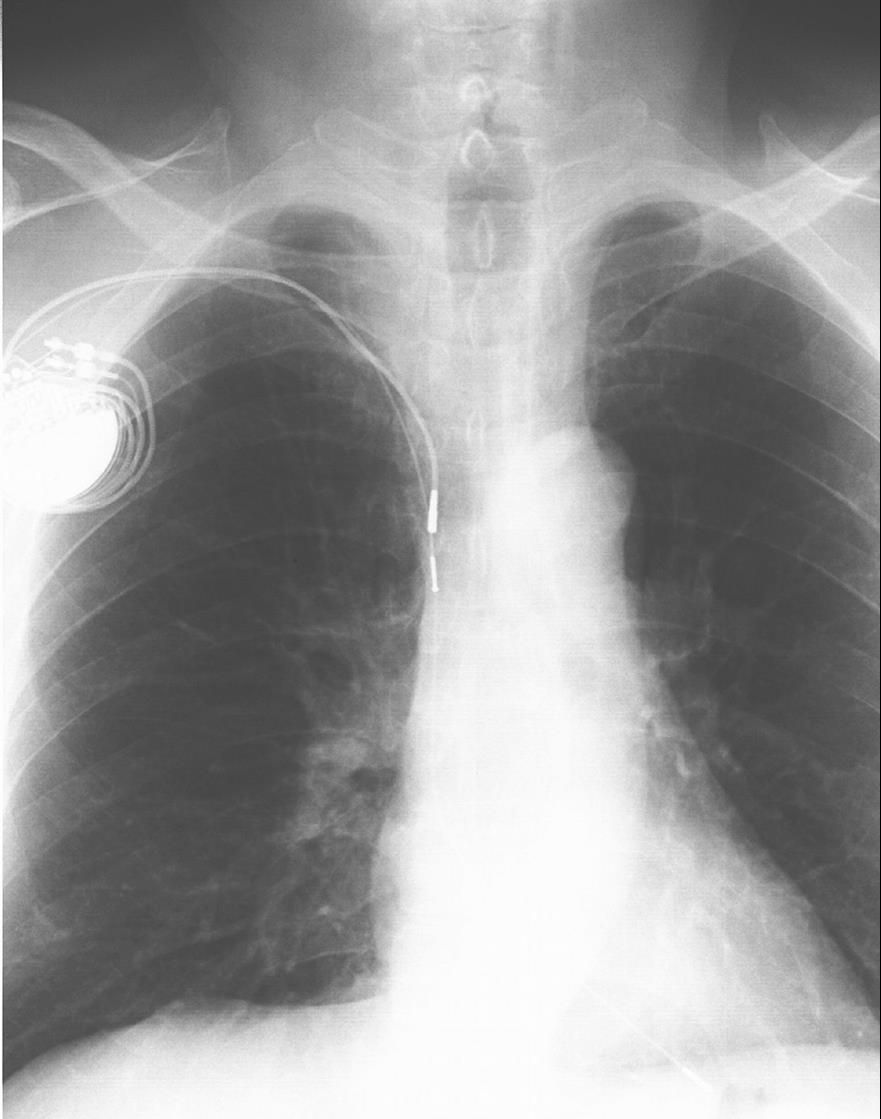

图1-17 囊袋感染

起搏器植入术后囊袋感染,脉冲发生器及导线外露。

国外文献报道囊袋感染主要与手术时的无菌操作、是否发热、有无早期手术干预(如导线移位复位等)以及临时起搏器有关。一旦发生囊袋感染,会给患者带来很大痛苦,而且医师处理也非常棘手,因此预防感染非常重要,加强无菌概念、控制患者全身情况、选择合适的植入部位、制作大小合适的囊袋等可减少其发生率。